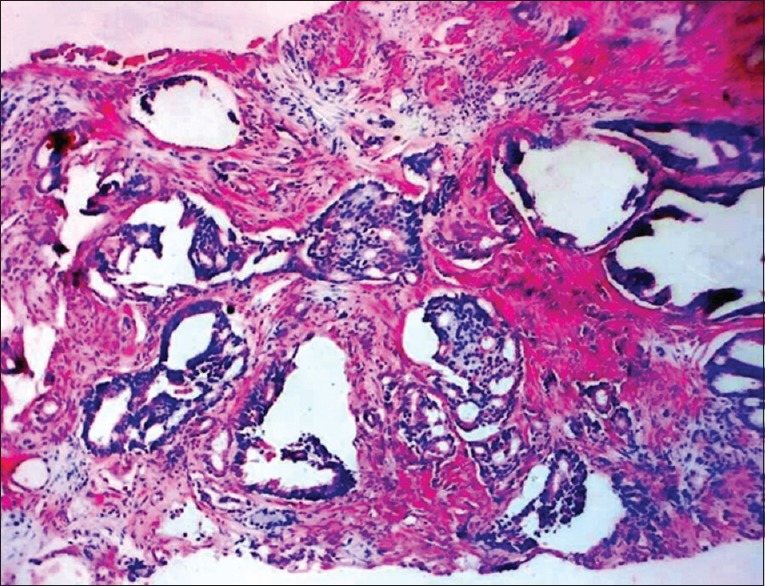

Prostate cancer remains the most common noncutaneous cancer in men, especially in this era of prostate-specific antigen assay. Prostate cancer metastases have been known to commonly affect the lymphatics, bones, and lungs. Prostate cancer metastasis to the skin is very rare (<1%) and often signifies a terminal disease. Involvement of the skin has been thought to be through lymphatic spread by embolization or permeation, hematogenous spread, and implantation during surgery (port site in radical prostatectomy). We report a 74-year-old man on management for advanced prostate cancer with subcutaneous goserelin (Zoladex) but developed skin metastasis in the course of treatment. The skin metastasis in our patient, however, was initially localized to the site of the regions of subcutaneous goserelin injection that we imagined if there is a link between the two. We reviewed the literature and currently found no connection. Is there truly a link?